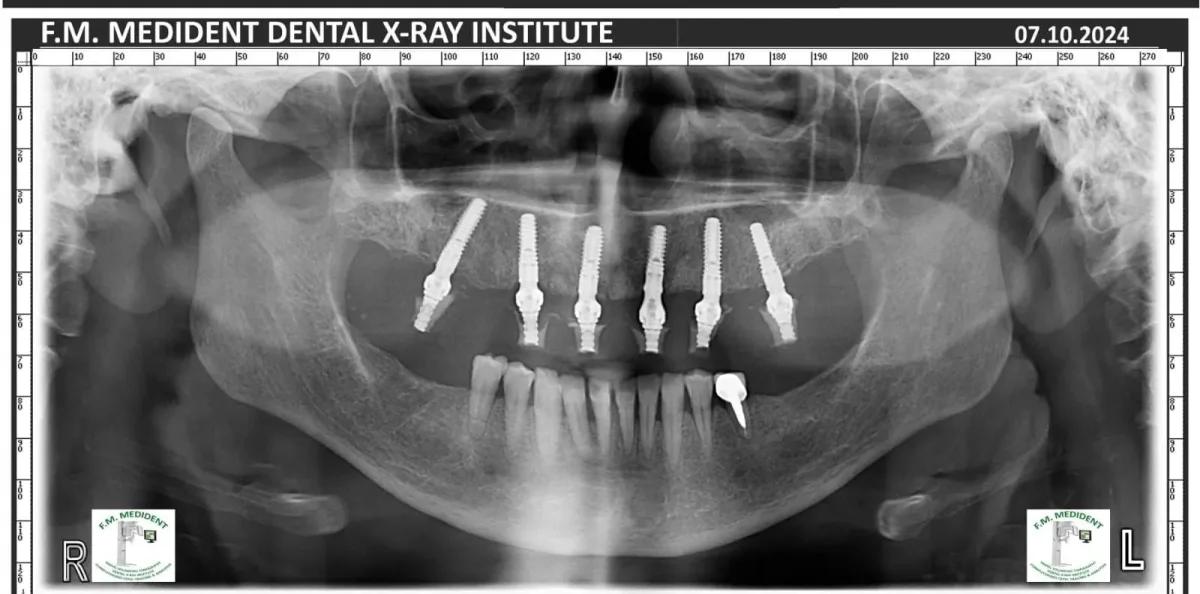

Cazuri reale înainte și după, din tratamente realizate în clinică.

Înainte

După